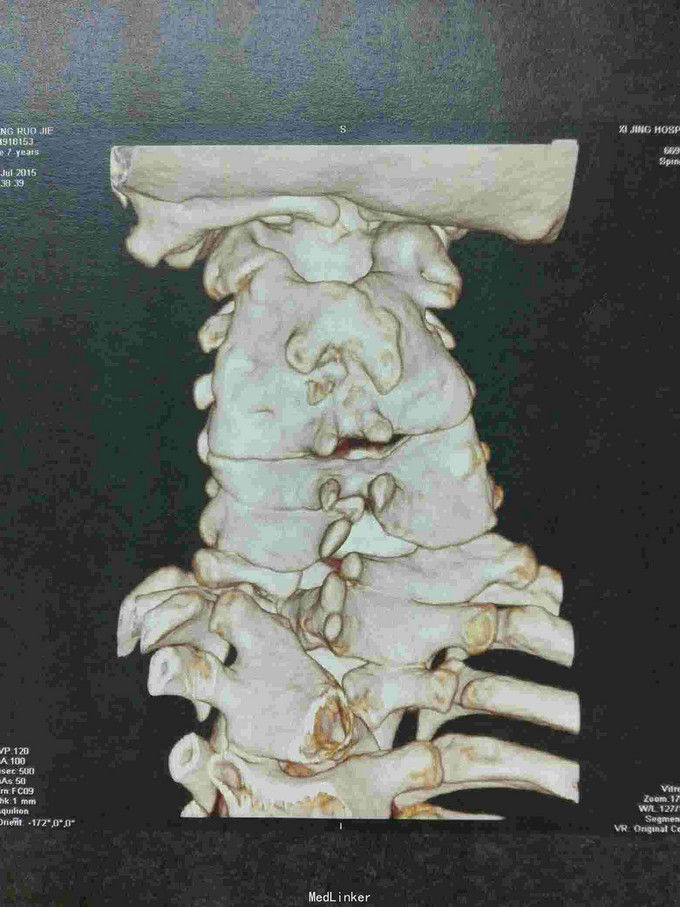

先天脊柱畸形

先天脊柱畸形8年。

严重脊柱畸形病例

先天性脊柱侧凸畸形

脊柱先天畸形